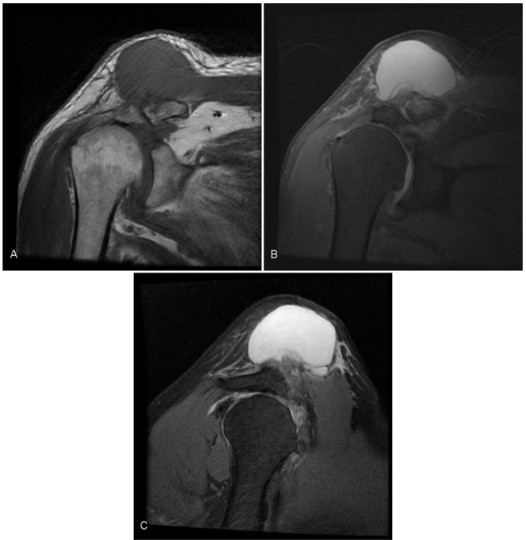

El segundo caso correspondió a un paciente de 70 años del sexo masculino, con una tumoración pétrea de hombro derecho, de dos meses de evolución, con aumento brusco de su tamaño. La RM mostró una tumoración quística, hipointensa en secuencias ponderadas en T1 e hiperintensa en DPFS, en estrecha relación con la articulación AC, de 60 mm de diámetro y rotura completa del tendón supraespinoso (fig. 3).

RM de hombro derecho, (A) coronal en secuencias ponderadas en T1, (B) coronal DPFS y (C) sagital DPFS. Formación quística con estrecho contacto con la articulación acromioclavicular, hipointensa en secuencias ponderadas en T1, hiperintensa en DPFS, asociada a rotura completa del tendón supraespinoso.